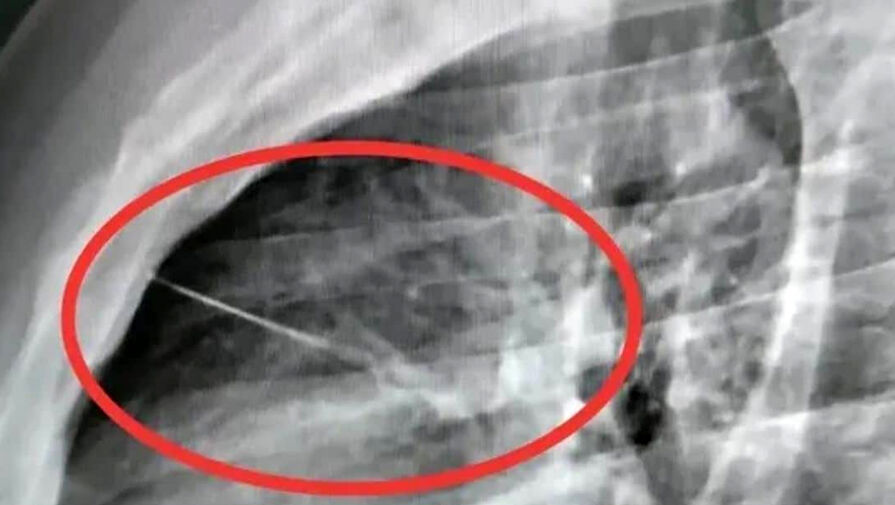

В Красногорской клинической больнице успешно извлекли швейную иглу из желудка 19-летней девушки, случайно проглотившей ее во время шитья. Об этом сообщили в пресс-службе медучреждения.

Пациентка вовремя обратилась за помощью, и бригада скорой доставила ее в стационар. Рентген брюшной полости показал инородное тело в желудке. Врачи первого хирургического отделения подготовили ее к экстренной операции, после чего с помощью современного оборудования эндоскописты аккуратно удалили опасный предмет, не допустив осложнений.